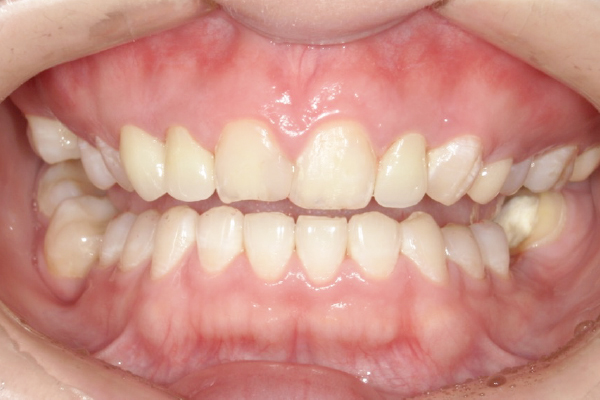

CASE1

セラミックを用いた虫歯治療

| 主訴 | 虫歯の治療と全体的な見た目の改善 |

|---|---|

| 治療期間 | 2ヶ月 |

| 治療費 | セラミック1本 88,000円〜165,000円(税込) デンタルローンで月3,000円から始められます |

| 治療の リスク | 治療には神経の治療や抜歯が必要な場合があります。 虫歯や歯周病を防ぐ為に、定期検診にご来院いただきます。 |